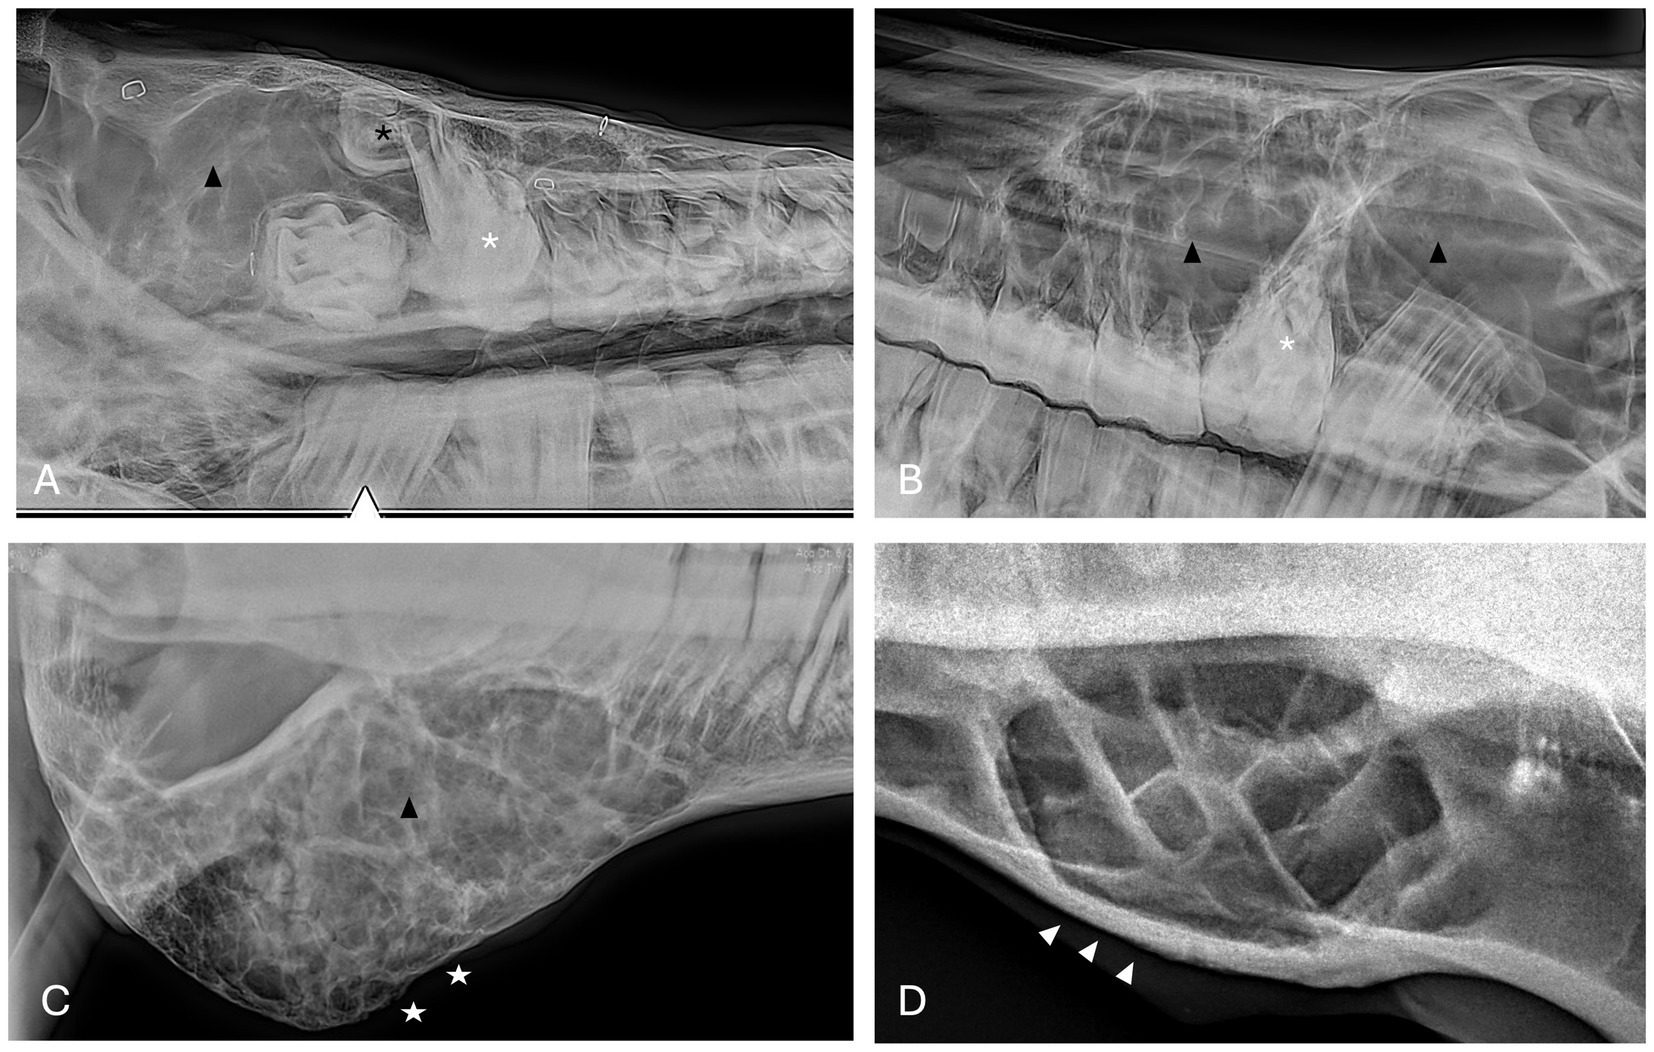

Radiographic findings are reported based on lesion type (Table 4) and location (Table 5). The most prevalent radiographic finding was tooth involvement in 16/17 (94.1%) cases followed by multiloculated lesions and increased soft tissue opacity in 14/17 (82.4%) cases, respectively (Figures 2–4). Rarefication of the surrounding bone (cortical thinning) was the third most common imaging finding identified in 13/17 (76.5%) of cases. All lesions had tooth involvement except for 1 bone cyst lesion. Radiographically unerupted teeth were 100% associated with dentigerous cysts (6/6) of which 83% (5/6) of the unerupted teeth were dysplastic (Figure 2). Thirty-three percent (2/6) of dentigerous cysts were associated with additional irregular dental material, and both of these lesions were located within the rostral maxilla (Figure 2). Dysplastic teeth also occurred in 2/6 (33%) of bone cysts (Figure 3). Abnormal dental findings were more closely linked to lesion type than location in the mouth.

Figure 2. Dentigerous cyst radiographic findings. (A,B) Case 2 multiloculated, well circumscribed dentigerous cyst containing irregular dental material (black arrows) associated with unerupted and dysplastic 104 (white asterisk), with rarefication of surrounding bone (white star) Images courtesy of Dr. Robert Baratt. (C) Case 9 multiloculated, well circumscribed dentigerous cyst containing irregular dental material (black arrows) associated with unerupted and dysplastic 306 (white asterisk) with osteosclerosis of adjacent bone (white arrowheads) Image courtesy of Easley equine dentistry. (D) Case 16 unilocular, well circumscribed dentigerous cyst associated with unerupted and dysplastic 307 (white asterisk), with osteosclerosis of adjacent bone (white arrowheads), and sunburst reaction (white arrows).

Figure 3. Bone cyst radiographic findings. (A) Case 3 multiloculated, poorly circumscribed bone cyst associated with dysplastic right maxillary first molar (white asterisk) and denticle (black asterisk) with increased soft tissue opacity (black arrowhead) and secondary sinusitis. Image courtesy of Easley equine dentistry. (B) Case 7 multiloculated, well circumscribed left caudal maxillary/paranasal sinus bone cyst associated with dysplastic left maxillary first molar (white asterisk) with increased soft tissue opacity (black arrowheads) and secondary sinusitis. Image courtesy of Easley equine dentistry. (C) Case 10 right caudal mandibular multiloculated, well circumscribed right caudal mandibular bone cyst with increased soft tissue opacity (black arrowhead) and rarefication of surrounding bone (white stars). Image courtesy of Easley equine dentistry. (D) Case 8 multiloculated, well circumscribed left mandibular bone cyst with osteosclerosis of surrounding bone (white arrowheads).

Figure 4. Radicular cyst radiographic findings. (A) Case 5 multiloculated, well circumscribed (white arrows) radicular cyst associated with dysplastic right maxillary second premolar (black asterisk) with increased soft tissue opacity (white asterisks), nasal passage involvement, and rarefication of surrounding bone (black arrow). (B) Case 15 multiloculated, well circumscribed (white arrows) radicular cyst associated with complicated crown fracture of left maxillary first molar (black asterisk) with associated increased soft tissue opacity (white asterisks). (C) Case 14 multiloculated, poorly circumscribed radicular cyst associated with a periapical lucency of the left maxillary second molar (black asterisk) with associated increased soft tissue opacity (white asterisks).

Rarefication of the surrounding bone was the most common radiographic bony change identified in 13/17 (76.5%) of cases (Figure 2). Osteosclerosis of adjacent bone occurred in 7/17 (41.2%) of cases while osteolysis of adjacent bone occurred in 6/17 (35.3%) of cases (Figure 5). Rarefication of the surrounding bone was most commonly associated with dentigerous cysts (5/6; 83.3%) and bone cysts (5/6; 83.3%). Osteosclerosis of adjacent bone was observed most frequently in the body of the mandible with 5/7 (71.4%) of cases affected. Osteolysis of adjacent bone was most frequently observed in the caudal maxilla/paranasal sinuses (3/5; 60%) and in bone cysts (4/6; 66.6%). Dentigerous cysts were the only type of lesion in this study to have an osteoproductive appearance with 4/6 (66.6%) cases of dentigerous cysts affected. Sunburst reaction was observed in a single case of a mandibular body dentigerous cyst (Figure 2).

Figure 5. Unclassified, radiolucent inflammatory lesions (A) Case 6 unilocular, well circumscribed (white arrows) inflammatory lesion involving the mandibular incisors and canines with associated increased soft tissue opacity (white asterisk), osteosclerosis of adjacent bone and cystic cavity packed with debris. Image courtesy of Dr. Laurelyn Kenner. (B) Case 12 unilocular, well circumscribed (white arrows), inflammatory lesion involving left mandibular incisors and canine with increased soft tissue opacity (white asterisk), osteosclerosis of adjacent bone (white arrowhead) and osteolysis (black arrowheads). Image courtesy of Dr. Jessica Hunt.

Increased soft tissue opacity was most commonly observed in dentigerous cysts (5/6) and unclassified, radiolucent inflammatory lesions (2/2) (Figure 5). All lesions located in caudal maxilla/paranasal sinuses, rostral maxilla and rostral mandible had increased soft tissue opacity (Figures 3, 4). Nasal passage involvement was observed in 4/5 cases in the caudal maxilla/paranasal sinuses and in 1/3 of cases located in the rostral maxilla (Figure 4). Radicular cysts were the most common lesion type associated with nasal passage involvement with 2/3 cases affected (Figure 4). Secondary sinusitis was observed in all cases located in the caudal maxilla/paranasal sinuses. Sixty-six percent of radicular cysts (2/3) demonstrated secondary sinusitis.